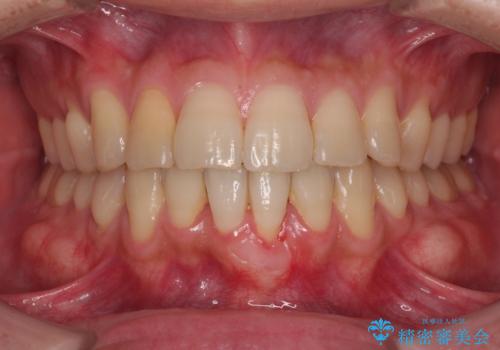

一度の処置で十分に根面被覆ができました。

舌側に歯石が溜まりやすく、やや出血が認められるため、定期的なクリーニングが大切となってきます。